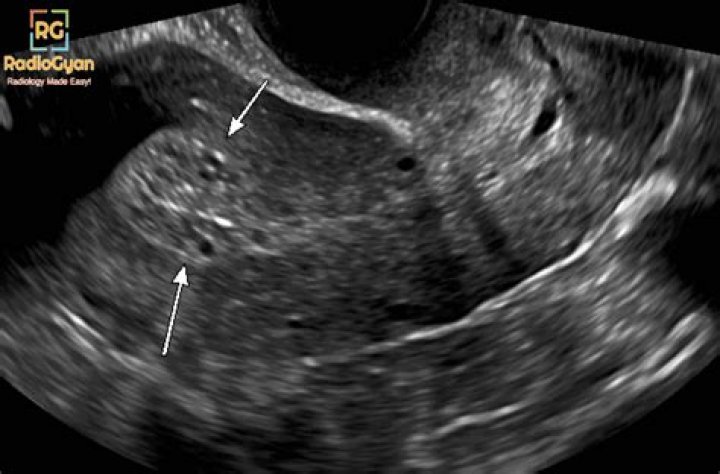

Is endometrium thick before period?

The part of your cycle between when you ovulate and when your period starts is called the secretory phase. During this time, your endometrium is at its thickest. The stripe accumulates fluid around it and, on an ultrasound, will appear to be of equal density and color throughout.

What is the normal size of endometrial thickness?

suggested upper limit of normal is <5 mm. the risk of carcinoma is ~7% if the endometrium is >5 mm and 0.07% if the endometrium is <5 mm. on hormonal replacement therapy: upper limit is 5 mm.

Among postmenopausal women with vaginal bleeding, an endometrial thickness ≤ 5 mm is generally considered normal, while thicknesses > 5 mm are considered abnormal4, 5.